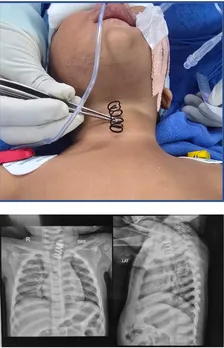

एम्स के डॉक्टरों ने 14 महीने के बच्चे की फूड पाइप से 2 इंच लंबा मेटल स्प्रिंग निकाला